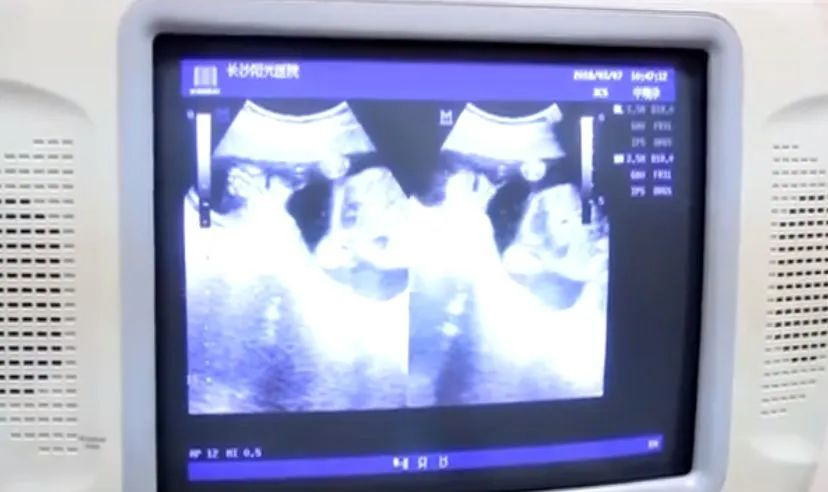

一位二十多岁的女士,因时常出现月经紊乱的情况,并伴随着出汗、心烦等症状。到医院检查激素指标后,没想到竟被确诊为卵巢早衰。医生介绍说,“卵巢已经萎缩了,呈薄片状,像50岁人的卵巢。”从B超结果来看,这位女士将因此可能失去生育能力。